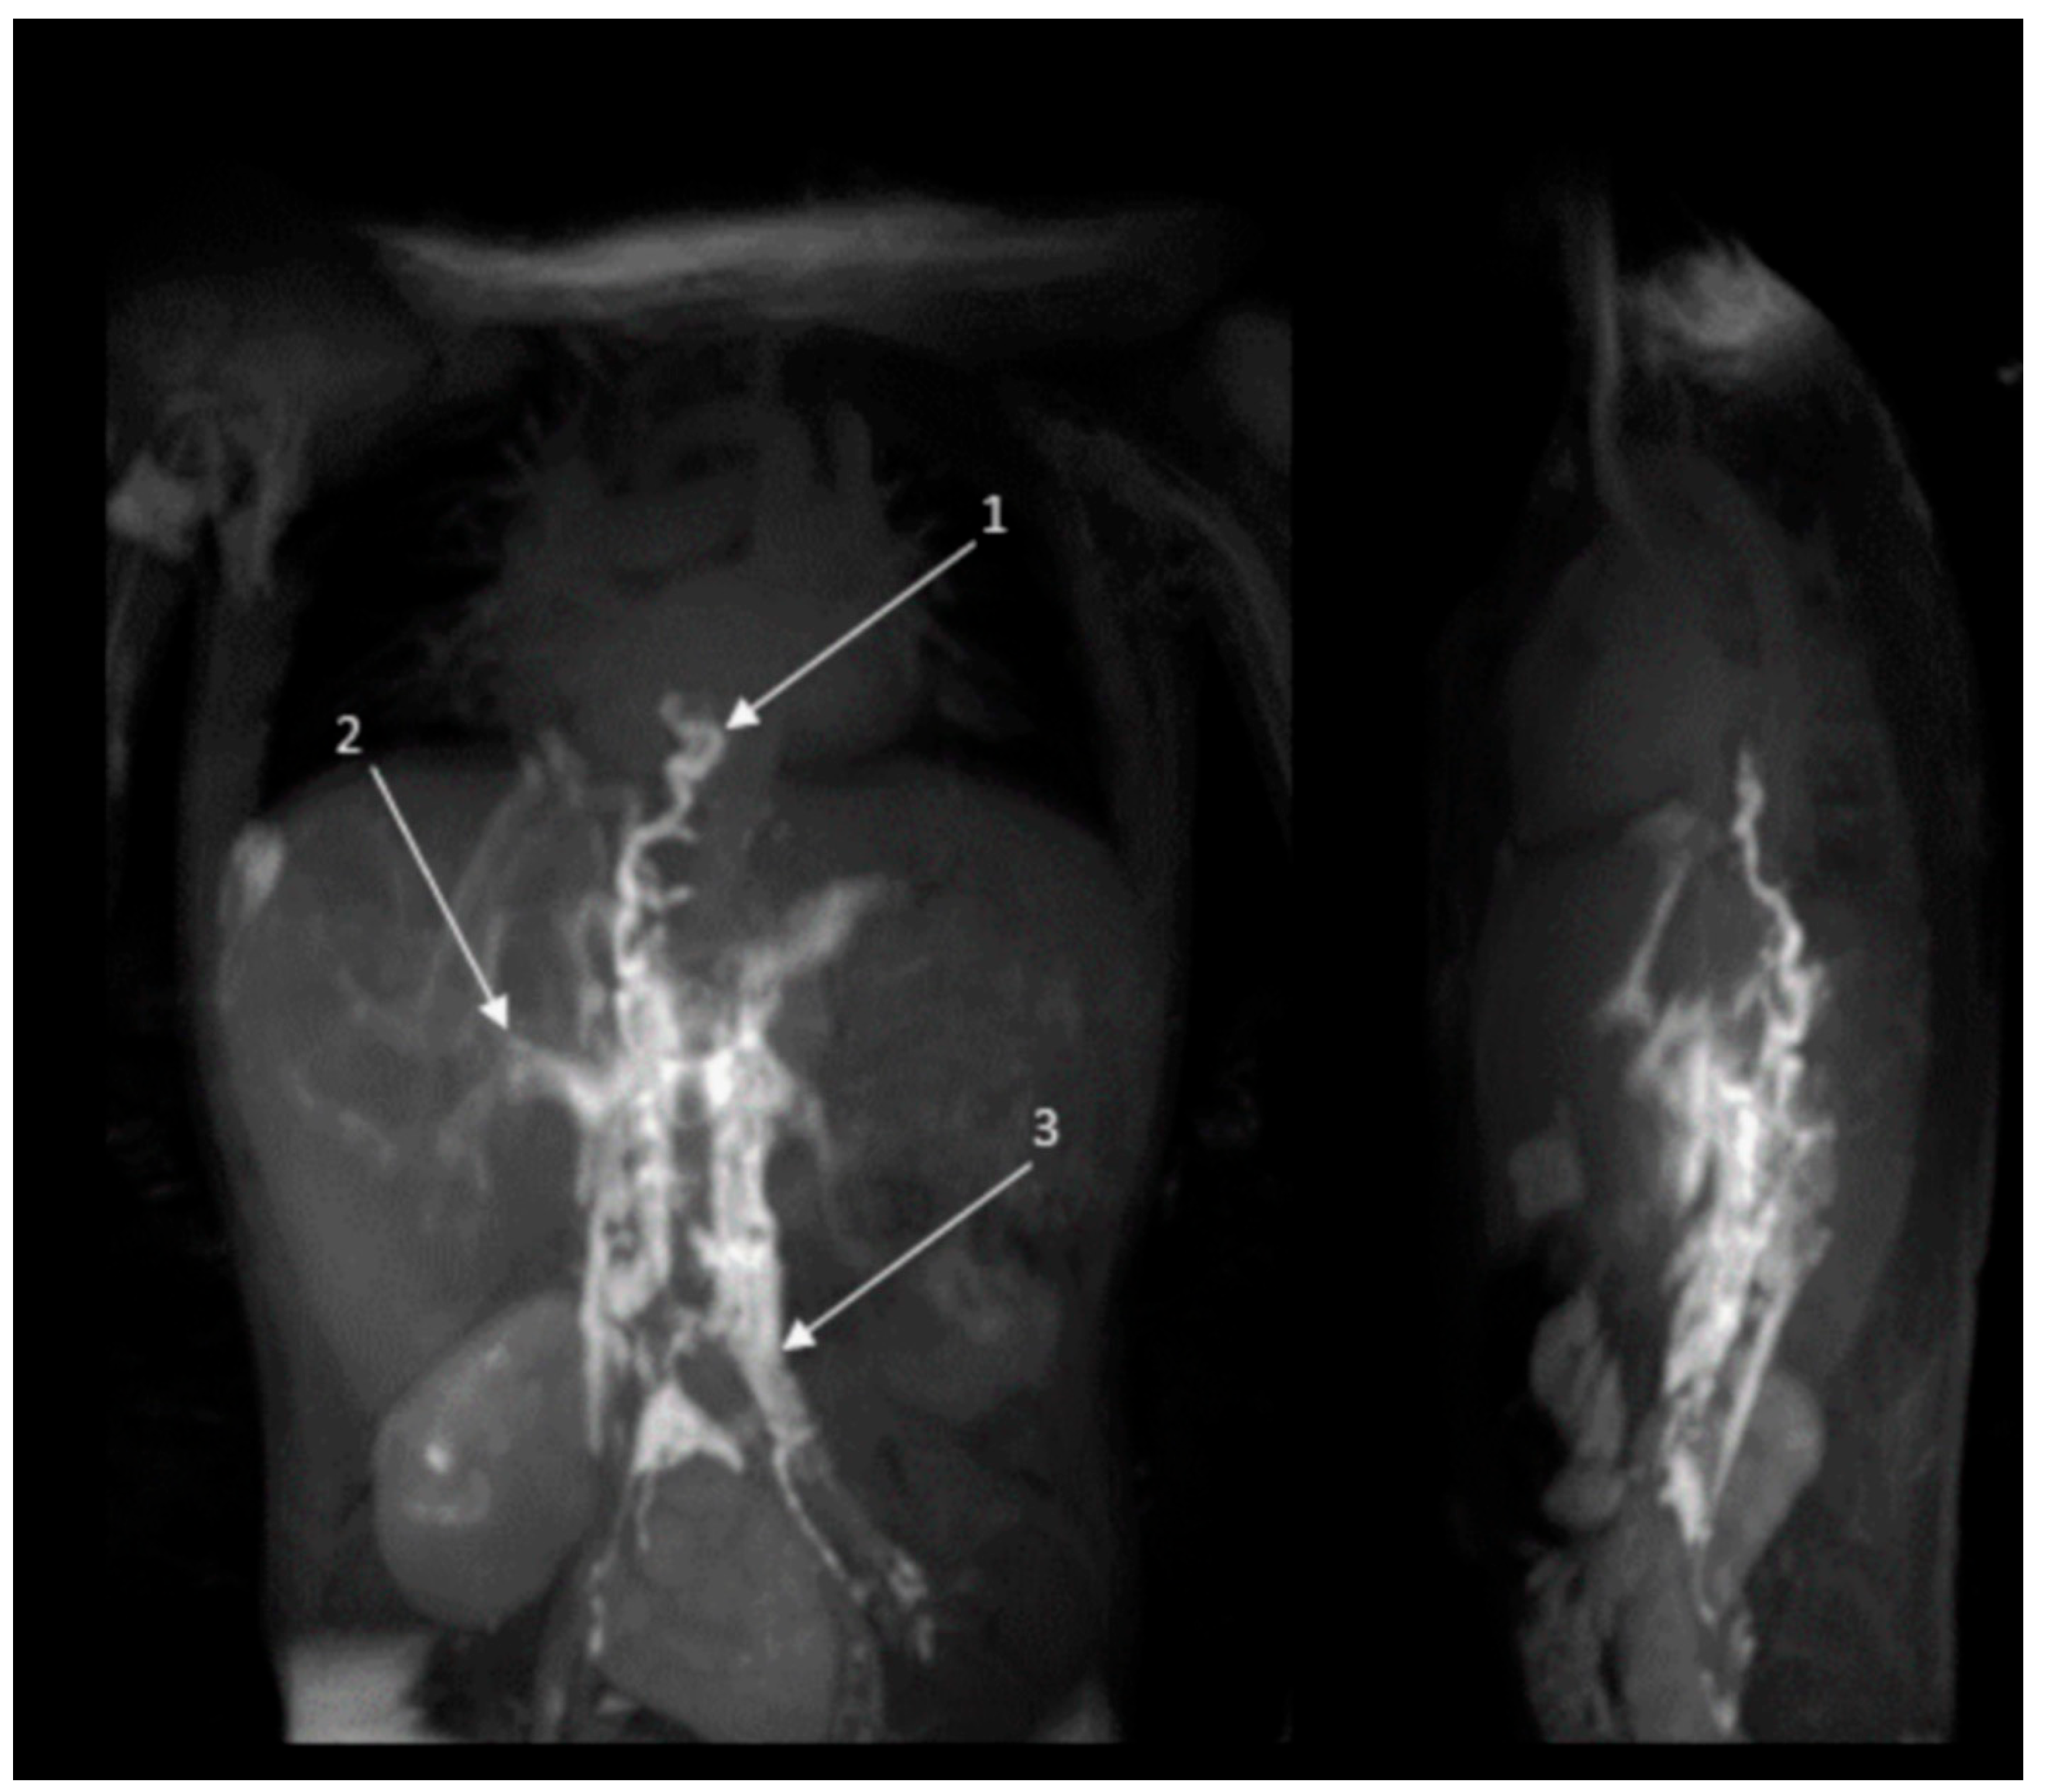

2.2.2. Radiology Assessment Before and After Treatment